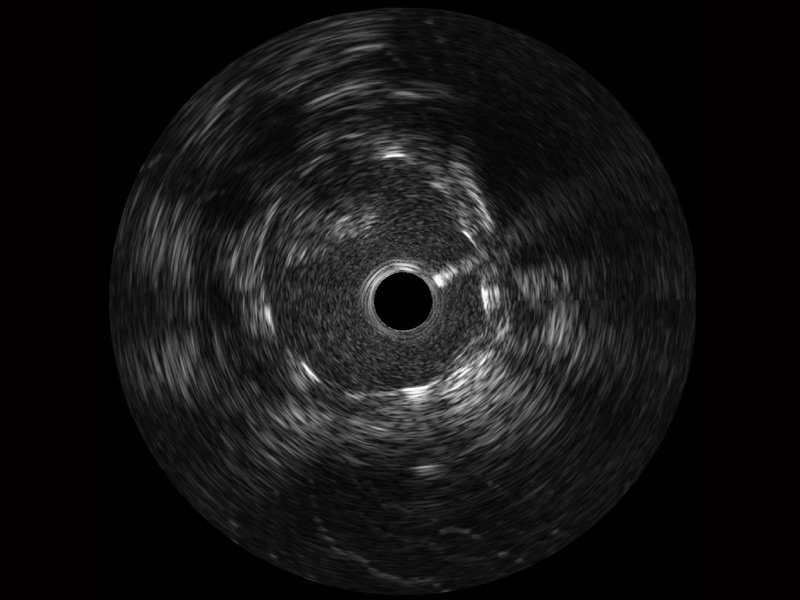

银河集团官网宽频IVUS图像

传统IVUS图像

对比传统IVUS导管成像,银河集团官网宽频IVUS图像的近场支架梁显影更细腻,远场中膜外血管仍清晰可辨,兼顾远中近,兼顾分辨力与穿透深度